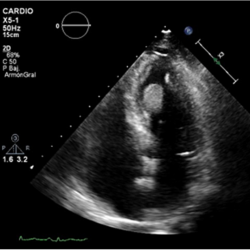

Figure 2.

Echo-contrast was administered, showing perfusion of the mass, excluding the diagnosis of thrombus.